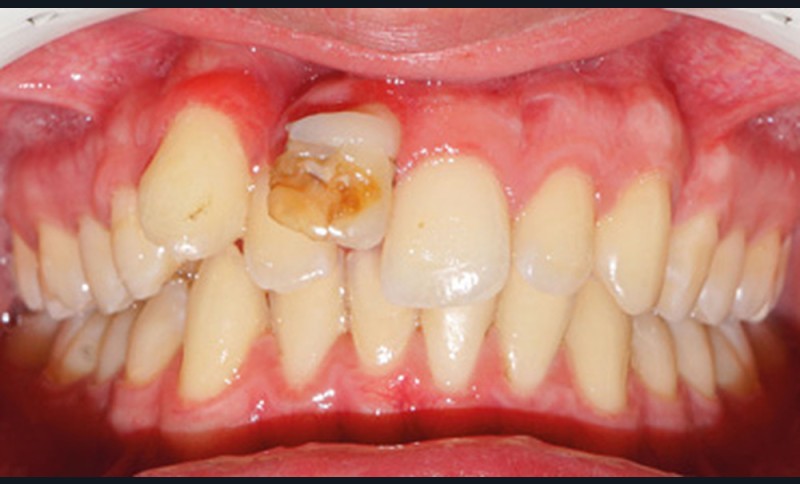

À l’examen clinique, on observe un visage symétrique, et un profil équilibré, avec un léger excès vertical de l’étage inférieur, induisant une incompétence labiale au repos (fig. 1a).

D’un point de vue occlusal, le patient, en denture adulte jeune stable, présente une classe II d’Angle bilatérale de 4 mm, associée à un encombrement maxillaire de 5 mm et mandibulaire de 2 mm. La face mésiale de 21 est centrée avec le plan sagittal médian, la non-concordance des médianes incisives est d’origine mandibulaire (déviation de la médiane mandibulaire vers la gauche) (fig. 1b-d).

Son incisive centrale supérieure droite (11) présente un défaut de structure amélaire sévère, compromettant une technique restaurative pérenne a minima. L’examen de la panoramique (fig. 1e) et de la radiographie rétroalvéolaire de 11 (fig. 1f) objective une fracture coronaire verticale, ainsi qu’une racine grêle et courbe, peut-être en rapport avec un ancien traumatisme [1]. Le rapport couronne clinique/racine clinique est défavorable.